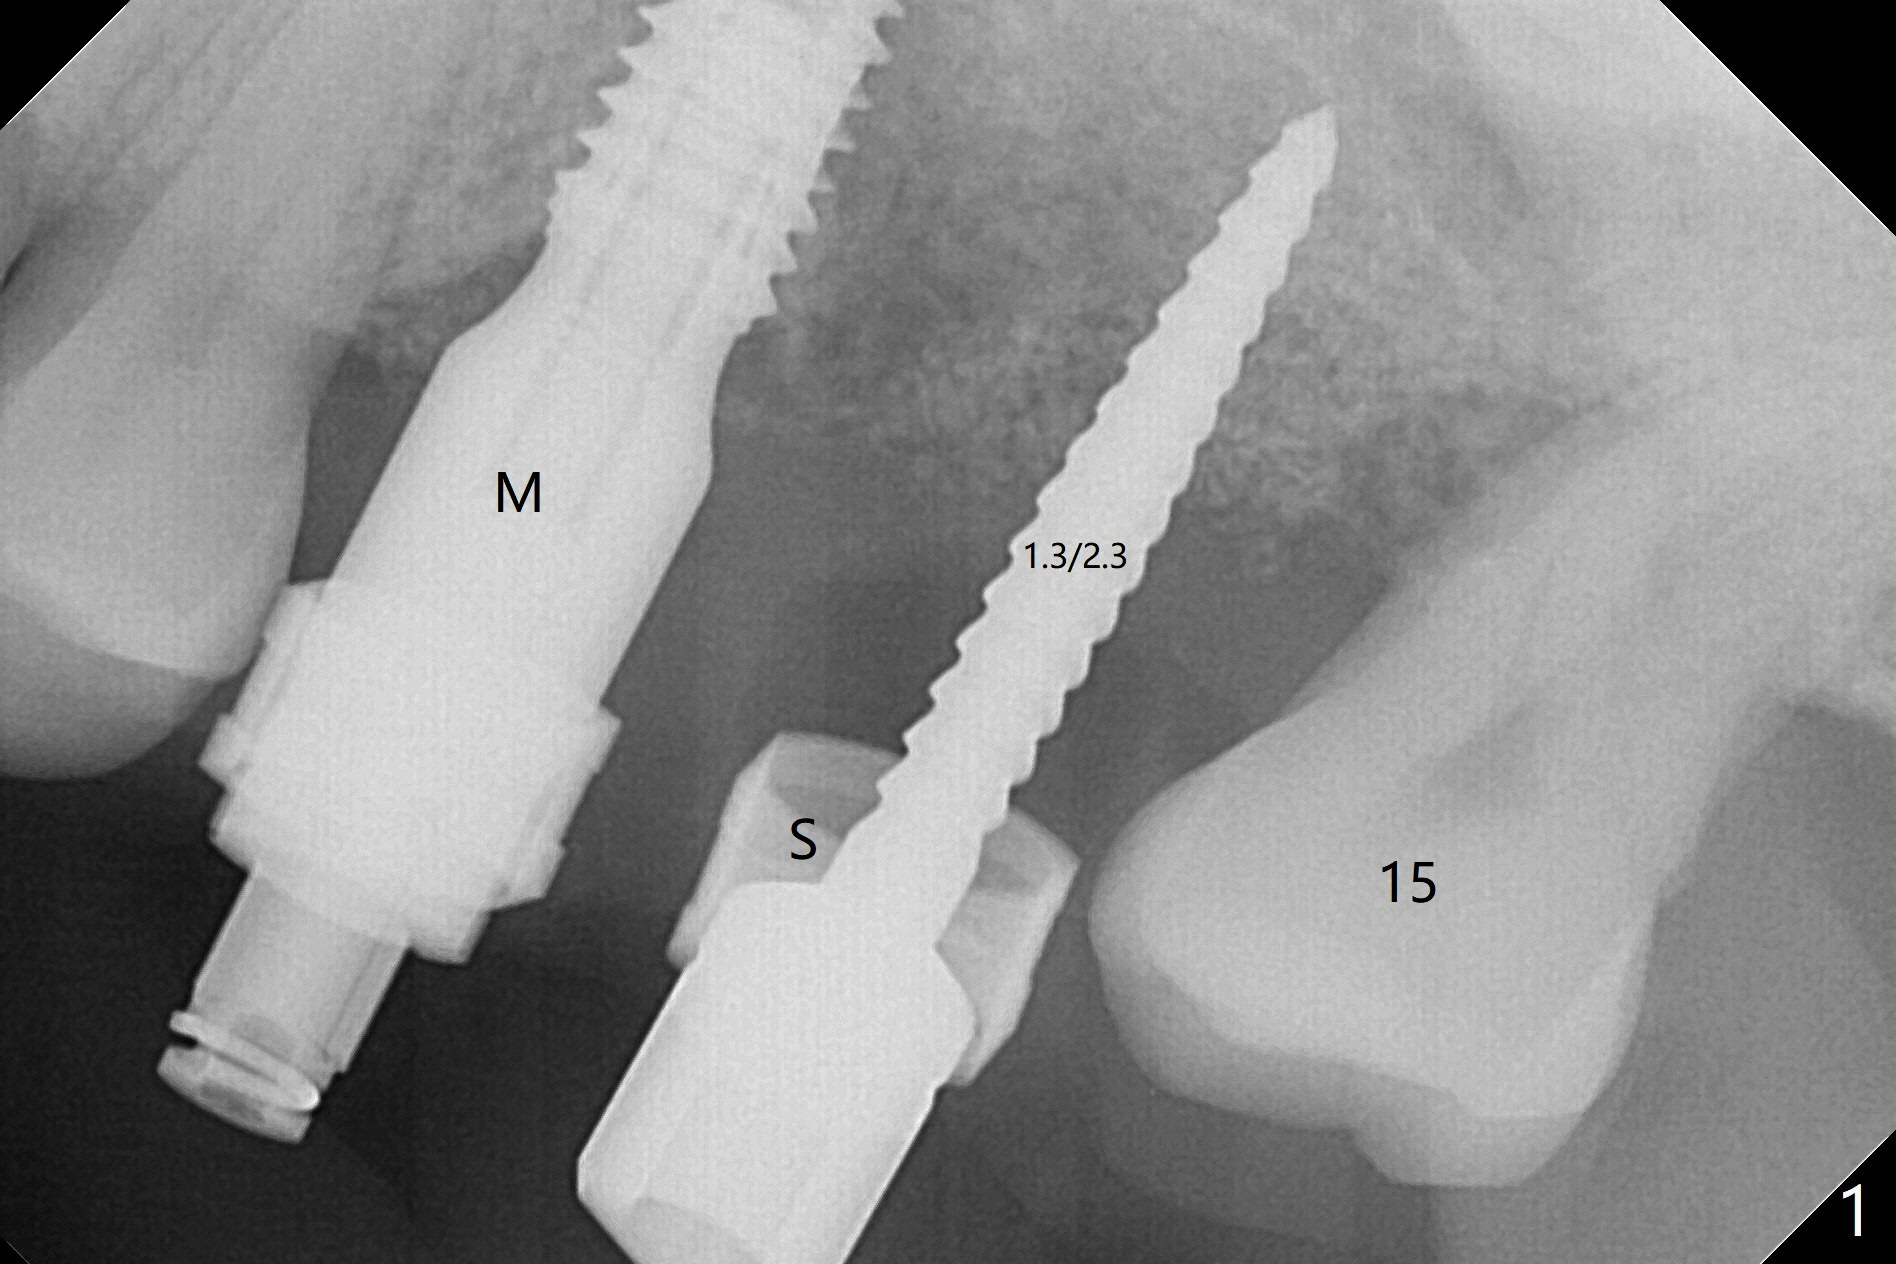

Four and a half months post implant removal, the patient returns for #14 implant placement. To increase bone density, bone expanders are used through the metal sleeve of the previous guide after use of 2.2x7.5 mm drill with 3 O-rings (1 mm shorter than previously designed; Fig.1). The osteotomy continues to form by bone expanders until 2.4/3.7 mm, followed by a 4x10 mm dummy implant (Fig.2-4). Finally a 4.5x7.3 mm implant is placed with ~ 25 Ncm with simultaneous sinus lift (Fig.5). There is no postop nasal hemorrhage. The implant dislodges with the healing abutment 2 months postop. The patient will return for follow up 3 months post 2nd loss. We are going to try again with PRF, UF guided sinus lift kit, sinus expander kit. After implant placement, use the implant at #13 and abutments at #13 and 14 to fabricate splinted provisional to hole the newly placed implant in place. Take preop PA and possible CT. In fact CT and impression are retaken for a new guide.